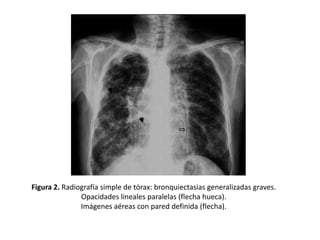

• Opacidades

lineales

paralelas

que

corresponden a bronquios dilatados con la

pared engrosada.

• Dan lugar al signo del “raíl de tranvía” (Figura

2, 3 y 4)

Figura 2. Radiografía simple de tórax: bronquiectasias generalizadas graves.

Opacidades lineales paralelas (flecha hueca).

Imágenes aéreas con pared definida (flecha).

Signos radiológicos • Opacidades lineales paralelas que correspondena bronquios dilatados con la pared engrosada. • Dan lugar al signo del “raíl de tranvía” (Figura 2, 3 y 4)

Figura 2. Radiografíasimple de tórax: bronquiectasias generalizadas graves. Opacidades lineales paralelas (flecha hueca). Imágenes aéreas con pared definida (flecha).